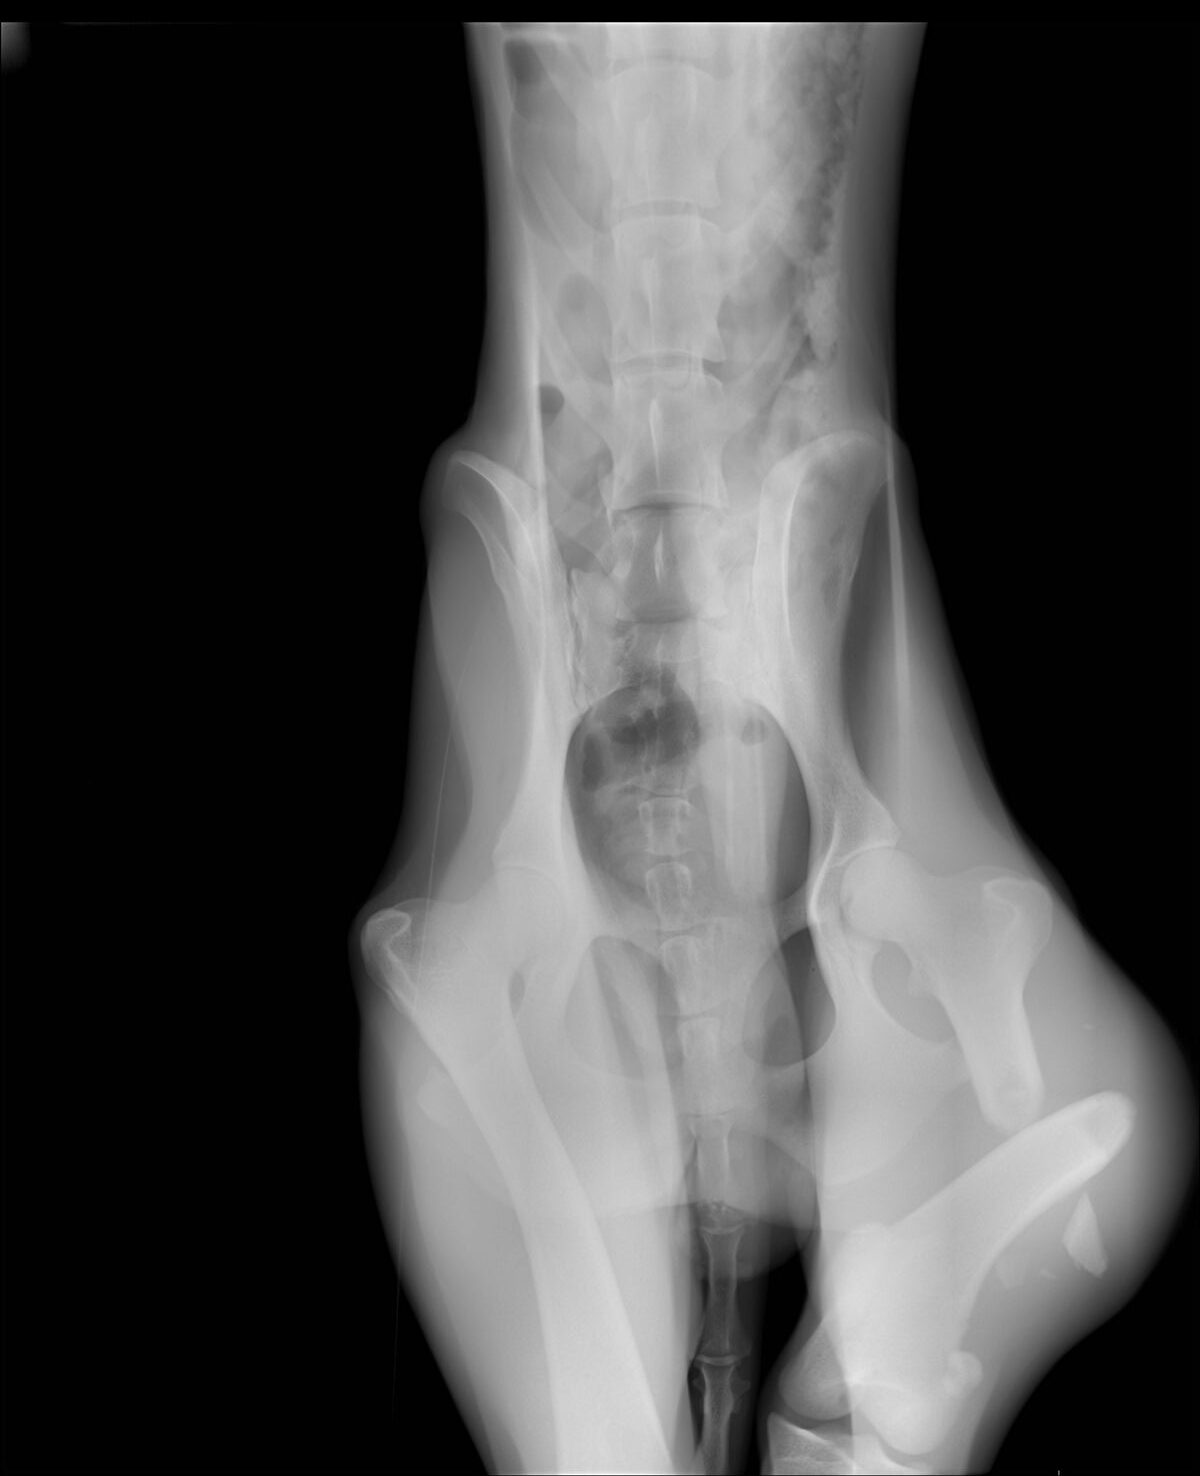

Marcus n’était plus qu’un véritable squelette, avec une fracture complexe du fémur au postérieur gauche. Il a dû vivre un véritable enfer, seul, blessé et affamé…

Il a été opéré en urgence à la clinique du refuge de la FBM, où il est actuellement en convalescence 🩺. La clinique est aujourd’hui totalement saturée, faisant face chaque jour à l’arrivée de nouveaux cas lourds : fractures, blessures graves, chiens brisés par la maltraitance et l’abandon… 😞 Malgré cette situation extrêmement difficile, Marcus a pu être pris en charge et bénéficie désormais de tous les soins nécessaires.